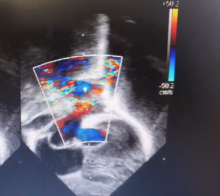

Once the corner anastomosis was done under vision, circulation was resumed. The atrial septal defect was closed with an untreated pericardial patch to increase the left atrial volume. The right atrium was closed. Sinus rhythm resumed after releasing the cross-clamp. The transoesophageal echo showed a wide anastomosis of common pulmonary vein and left atrium. In the transthoracic echo, a white arrow showed the ASD patch, and the yellow arrow showed the wide unobstructed anastomosis. The anastomosis was larger than the mitral valve area which is possible only under direct vision with this technique. The vertical vein to left atrial appendage anastomosis was also flowing well.